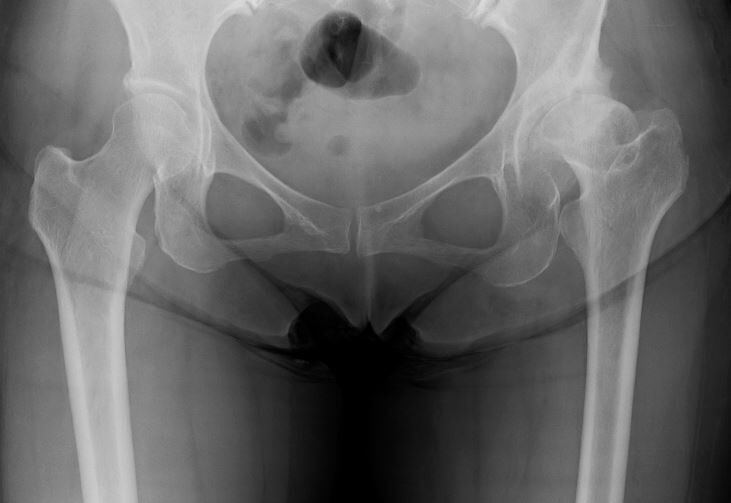

単純X線像ではたいしたことない症例に見えます。かなり小柄な方だったので、通常のインプラントで対応できるか確認する必要があるぐらいしか問題点を思いつきませんでした。

しかし、術前CTで寛骨臼の前方開角が45度、大腿骨頚部前捻角が40度でした...。大腿骨頚部前捻角はまだしも、寛骨臼前方開角は看過できません。